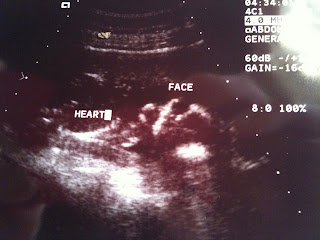

We went to our ultrasound today and it went perfect! Bo and I were so blessed by the opportunity to go to First Call and have Brook as our ultrasound tech. She did an amazing job and really knew what she was looking at. We got lots of pictures of our sweet baby girl and are so blessed by everything!

Everything looked great on the ultrasound and she is growing strong and healthy!!

Here are a few pictures of our little angel. She weighs about 3 ounces and is about 4 inches long.